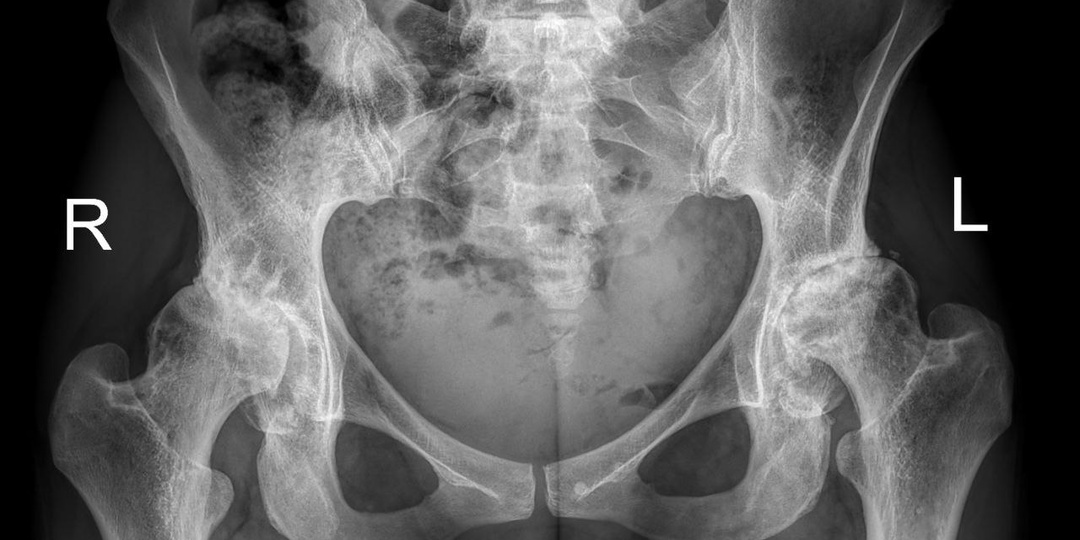

Каждый пациент приходит с собственной историей - и наша задача не просто провести операцию, а помочь человеку вернуться к привычному ритму жизни. К нам обратилась пациентка из Московской области. Её главная цель — как можно быстрее вернуться к активной жизни, ведь дома ждал маленький ребёнок. Медицинский анамнез: врождённая дисплазия с подвывихом, развившийся на этом фоне двусторонний коксартроз, выраженный износ тазобедренных суставов. Было принято решение о проведении одномоментной двусторонней замены тазобедренных суставов. Такой подход позволял сократить общее время реабилитации и быстрее вернуться к активной жизни. Особенности операции Для операции был выбран малоинвазивный доступ «бикини» - модификация прямого переднего доступа (DAA). Короткие ножки Metha позволили сохранить бедренный канал, так как пациентка молодая, с хорошим качеством кости. Роботизированная компьютерная навигация OrthoPilot обеспечила прецизионное позиционирование эндопротезов с точностью до миллиметра. Опера